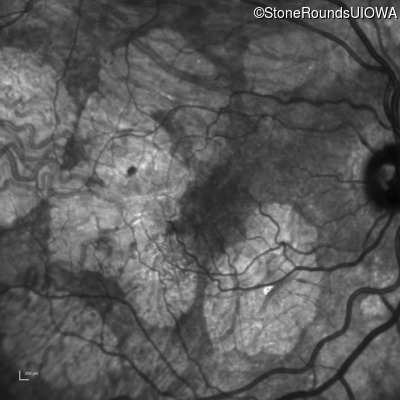

Infrared Fundus Photograph - Right - 20/40 -2

Exemplar

Infrared Fundus Photograph - Left - 20/40 +1